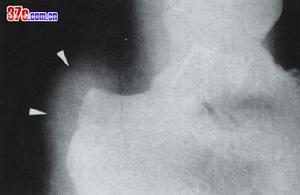

创伤引起的滑囊炎发病迅速,全身疾病引起者通常为逐渐发病。常见症状为跟骨后间隙疼痛,肿胀,发热,行走不便与穿鞋困难。开始时肿胀仅限于跟腱的前面,但很快扩展到内侧与外侧,跟腱附近肿胀。发热和疼痛原发于软组织内这两点可与距骨后结节骨折相鉴别。X线检查以排除骨折或类风湿侵蚀性跟骨变化。滑囊内注射可溶性皮质类固醇与麻醉剂,必须小心避免药物直接注入跟腱。热敷和休息也可以减轻疼痛。 医学百科网 | YxBaike.Com

跟腱前囊炎本病常见症状为跟骨后间隙疼痛,肿胀,发热,行走不便与穿鞋困难。开始时肿胀仅限于跟腱的前面,但很快扩展到内侧与外侧。临床上对本病的诊断一般根据其临床表现便可确诊,一般无须进行辅助检查,在一些特殊的病例或有疑似症状而为了排除其它疾病的存在时,可进行X线检查。

(2)排除骨折或类风湿侵蚀性跟骨变化,由于表现具有相似之处,帮对在鉴别上常借助一些辅助检查,最常用的是X线检查,可直接发现病损的地方。